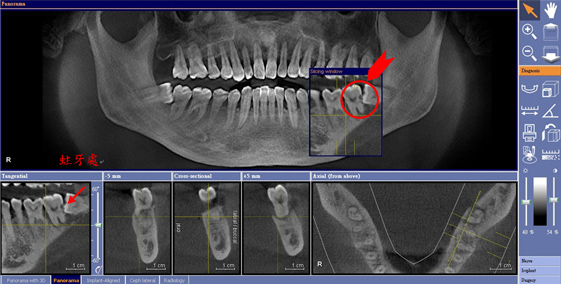

檢查水平智齒是否造成鄰牙蛀牙